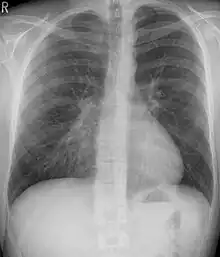

Pectus excavatum is initially suspected from visual examination of the anterior chest. Auscultation of the chest can reveal displaced heart beat and valve prolapse. There can be a heart murmur occurring during systole caused by proximity between the sternum and the pulmonary artery.[15] Lung sounds are usually clear yet diminished due to decreased base lung capacity.[16]

Many scales have been developed to determine the degree of deformity in the chest wall. Most of these are variants on the distance between the sternum and the spine. One such index is the Backer ratio which grades severity of deformity based on the ratio between the diameter of the vertebral body nearest to xiphosternal junction and the distance between the xiphosternal junction and the nearest vertebral body.[17] More recently the Haller index has been used based on CT scan measurements. An index over 3.25 is often defined as severe.[18] The Haller index is the ratio between the horizontal distance of the inside of the ribcage and the shortest distance between the vertebrae and sternum.[19]

Pectus excavatum on PA chest radiograph with shift of heart shadow to the left and radioopacity of the right paracardiac lung field

Chest x-rays are also useful in the diagnosis. The chest x-ray in pectus excavatum can show an opacity in the right lung area that can be mistaken for an infiltrate (such as that seen with pneumonia).[20] Some studies also suggest that the Haller index can be calculated based on chest x-ray as opposed to CT scanning in individuals who have no limitation in their function.[21]